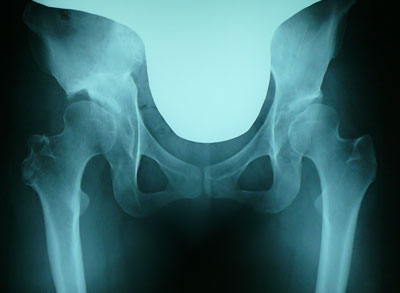

レントゲンチェック、とくに変わりなく。

本日のレントゲンです